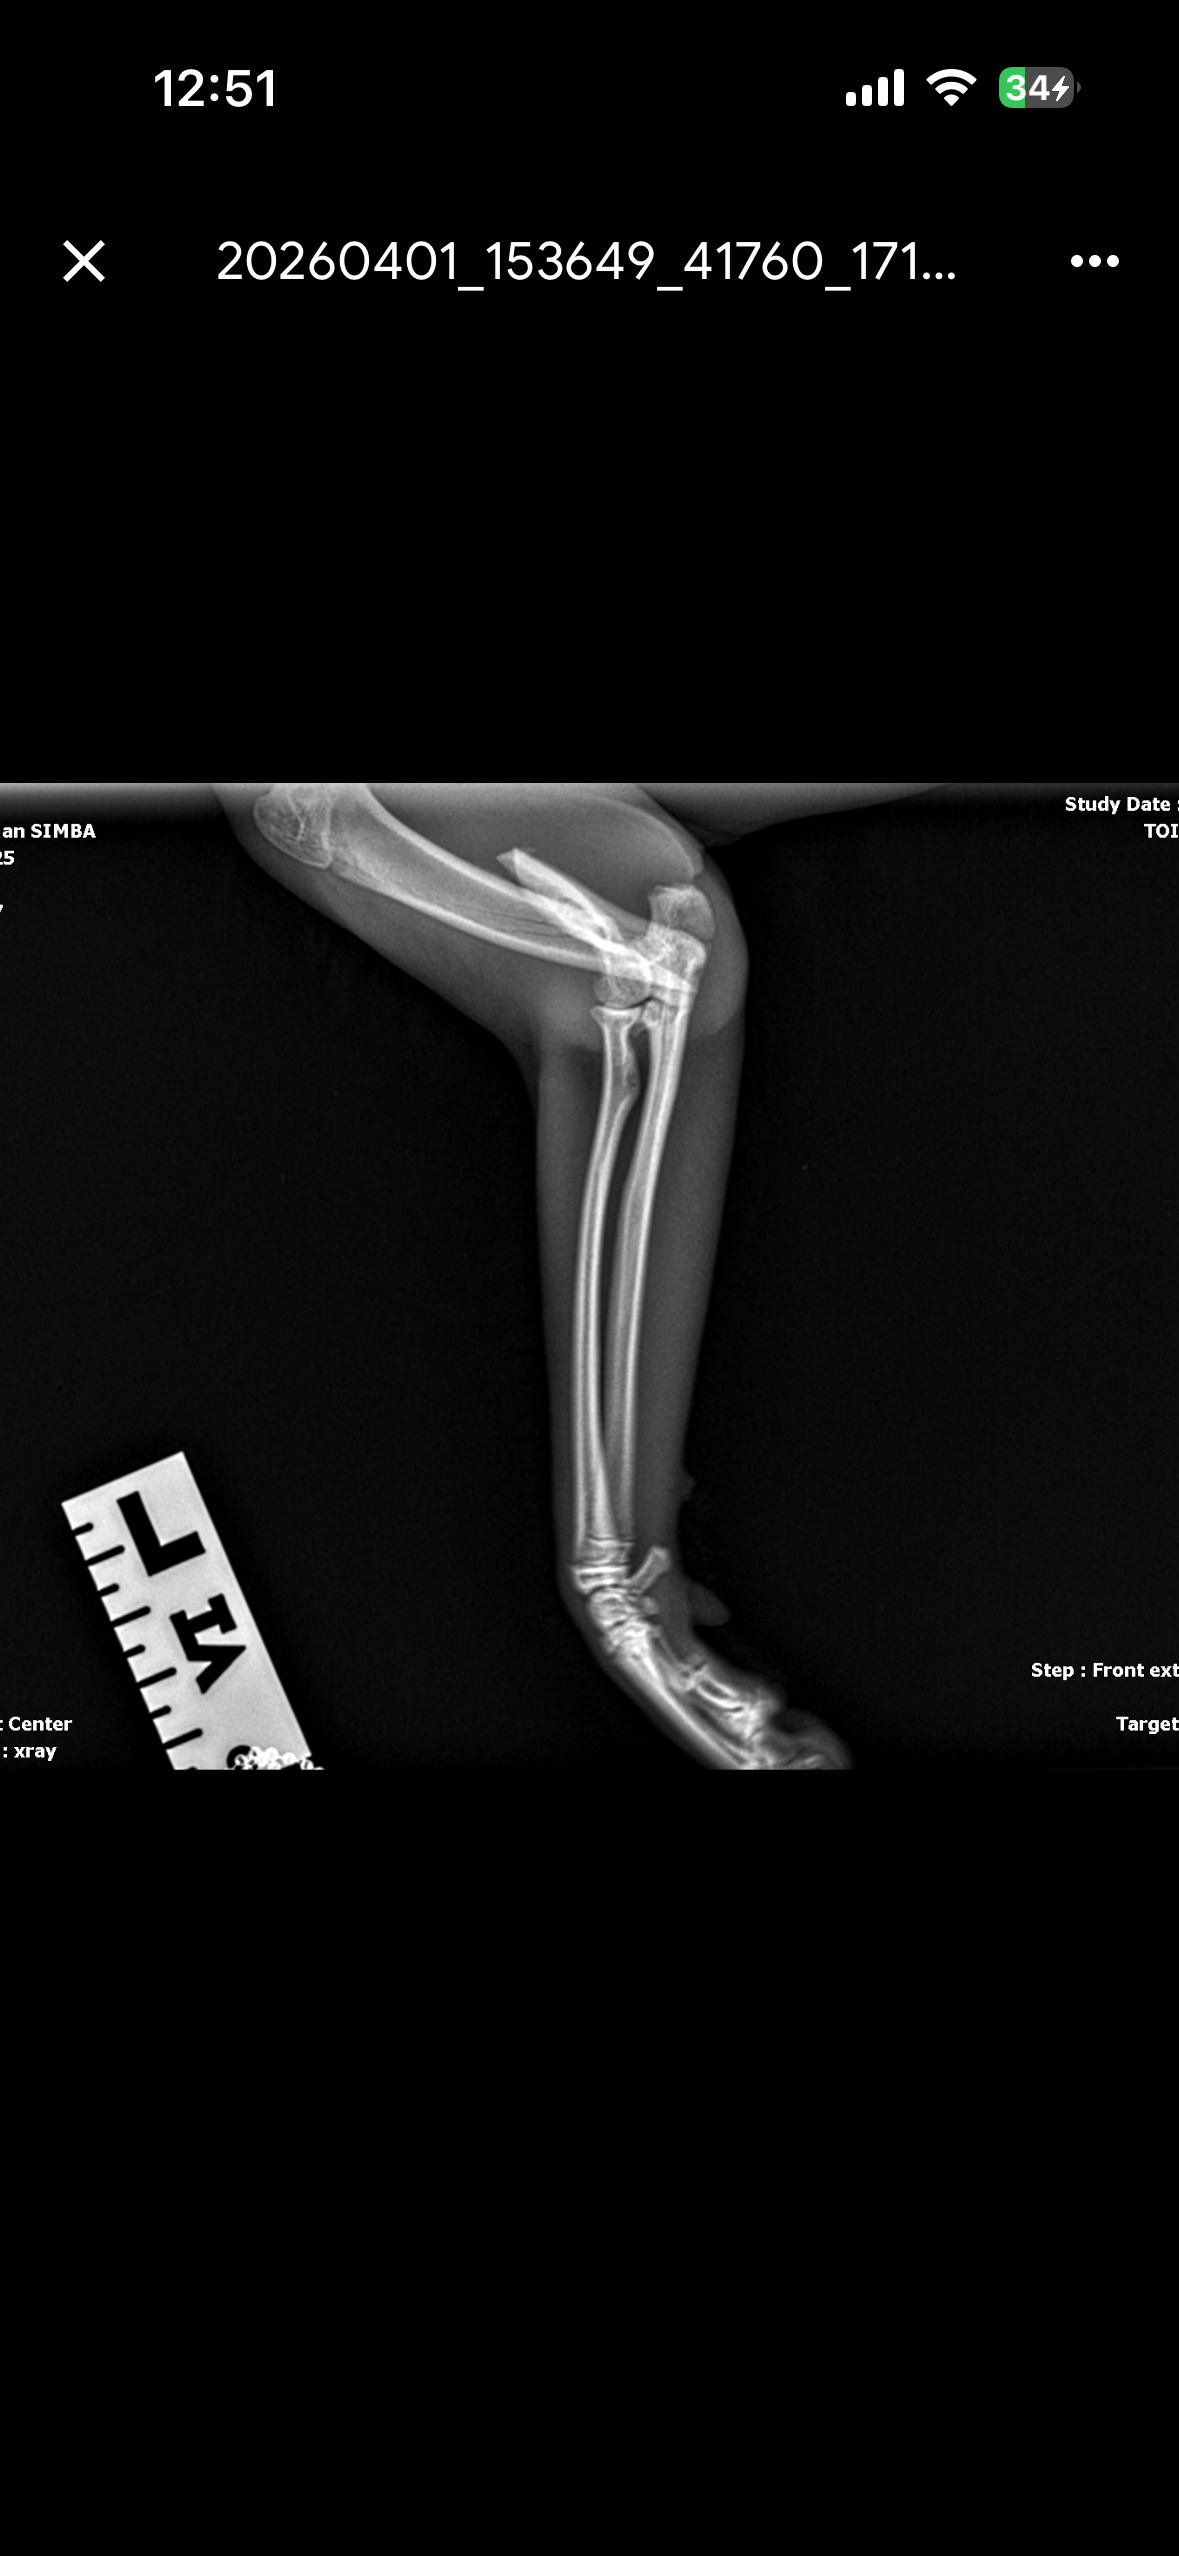

A few days ago, Simba managed to get outside and I found him with an injured arm. The vet says it’s broken and he needs urgent treatment. I’m doing everything I can to get him the care he needs, but the cost is more than I can afford right now. I have some funds set aside, but I’m still short and worried about how long it might take to get him the help he needs.